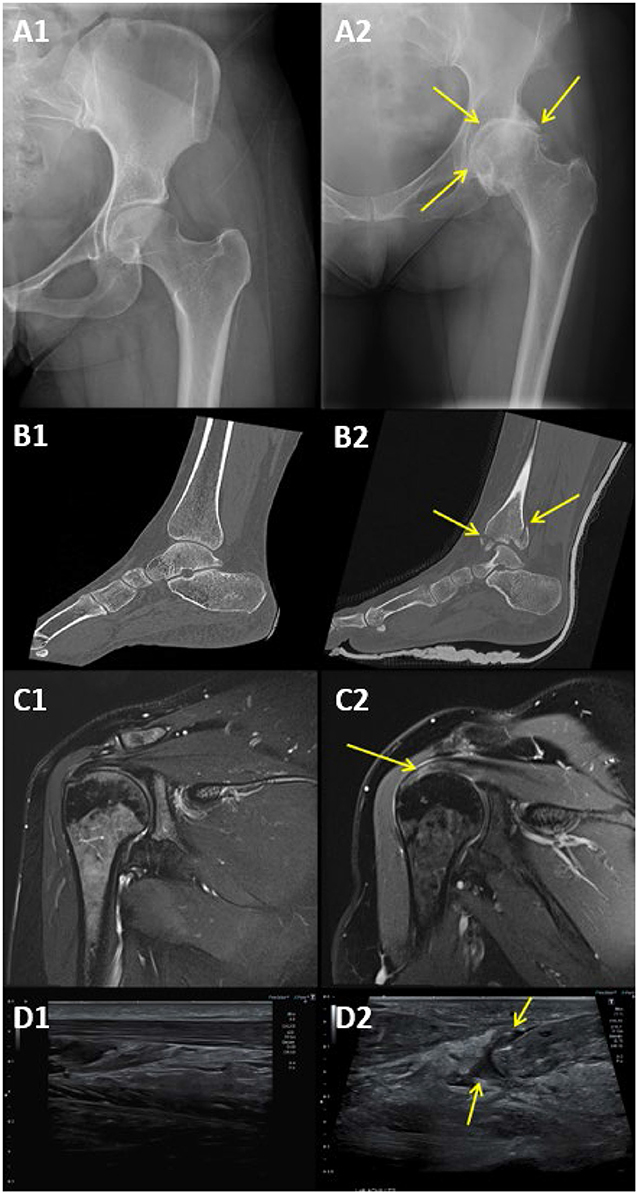

Sometimes, what feels like a musculoskeletal issue might actually be something else! For example, sometimes pain you feel in your bones and muscles can actually come from another part of the body, like the heart or the kidneys [1]. That is why doctors use different imaging techniques, not just to look at bones and muscles, but also to rule out other conditions that might be causing pain (Figure 1).

X-ray and MRI images display different joints with arrows pointing to specific areas. A1 and A2 show hip X-rays; A2 has arrows indicating Abnormalities caused by osteoarthritis. B1 and B2 present ankle scans, with B2 highlighting specific points that represent fractures. C1 and C2 are shoulder MRI images, with an arrow on C2 marking an area of tendon degeneration. D1 and D2 depict ultrasound scans, D2 has arrows pointing to an Achilles tendon rupture.

• Figure 1 - (A) X-ray of (A1) a healthy hip and (A2) hip osteoarthritis, pointed out by the yellow arrows.

• (B) CT of (B1) a healthy ankle and (B2) an ankle broken in multiple places, highlighted by yellow arrows. (C) MRI of (C1) a healthy shoulder and (C2) a shoulder with tendon degeneration, highlighted by the yellow arrow. (D) Ultrasound of a (D1) healthy Achilles tendon and (D2) a ruptured Achilles tendon, pointed out by the yellow arrows.